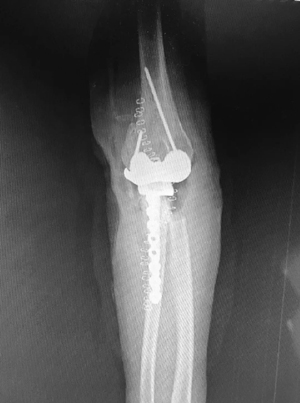

团队联合爱康医疗,以该患者的肘关节CT为基础,历经2个半月的设计和不断改良,考虑了关节稳定性、假体固定和骨长入等相关问题,定制了一套符合临床需求的肘关节表面置换假体(图2),患者也十分配合的耐心等待。4月14日上午八点四十,在麻醉科和手术室的全力配合下,这台手术终于顺利开台。蒋协远教授带领团队经过两个多小时的努力,手术顺利完成,术中患者的屈伸和旋转活动度均恢复至正常水平,并且关节稳定(图3)。目前患者正逐步康复中。

图3 患者术后肘关节正侧位片。